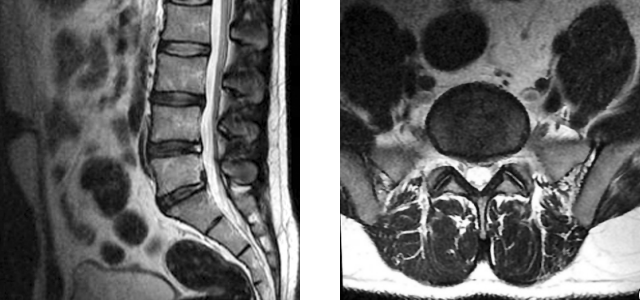

MRI shows herniation

The following morning Jane is able to have the MRI done and returns to see Dr. Kim. Dr. Kim reviews the MRI imaging with Jane, telling her she sees the expected bulge in the spinal disc that is pinching the sciatic nerve. This diagnosis confirms the cause of Jane’s lower back and leg pain. The technical term for this type of spinal disc herniation is an L5-S1 herniated nucleus pulposus. Dr. Kim refers Jane to a physical therapist, telling Jane that the therapy and pain reliever are the best ways to speed her recovery. After the ibuprofen regimen Jane was prescribed during her previous appointment has ended, Jane is to take two ibuprofen 200 mg over the counter as needed up to three times a day. She may stop taking ibuprofen completely as soon as her pain stops.

Jane had gone to Susan George for her physical therapy for four weeks and is no longer experiencing pain at this point. She has not had to take any pain medication in the previous week, and has returned to training for her excitedly anticipated Race for the Cure walk. Ms. George encourages her to continue to be active after the race is over as this is the best way of preventing reinjury, and the exercise will really benefit her in other ways. Jane returns to Dr. Kim and informs her that she had enrolled in a research study that the physical therapist introduced to her. As part of this study, Jane had new MRI imaging done and she shares them with Dr. Kim.

MRI shows healing

Dr. Kahn tells Jane that the images show what Jane feels, that all is now well with her.

In a nutshell: Imaging is not called for in the circumstances surrounding Jane’s initial visit. Sudden worsening of her pain is a reason for the need for imaging. MRI typically does a nice job of showing disc herniation. X-radiography does not, but is done to rule out other dangerous conditions that could be contributing to Jane’s symptoms. In Jane’s case the MRI is done first, and only if the MRI does not show the reason for her pain will an x-ray be necessary.

Imaging is not indicated in acute lower back pain or sciatica. One indication for MRIs and x-rays is sciatica that does not resolve in six weeks. An MRI becomes indicated for Jane when the condition suddenly worsened following the misstep on the stairs. Imaging after symptoms subside is contraindicated. It was done in this case only because Jane was in a research study which included an MRI as part of the study. The physical therapist told her of a study that matched her symptoms, and Jane decided she would like to enroll.

In asymptomatic individuals, about 20% will have findings of disc herniation, and about 30% will show a bulging disc. This lack of specificity of MRI as a tool utilized to diagnose these conditions makes an MRI unsuited to routine diagnostic use for lower back pain problems. There would be an unacceptable number of false positives. The physical exam is adequate for diagnosis except in cases where sciatica lasts 6 weeks, or where pain, numbness, or other indications make an MRI needed. At this point imaging is necessary to see more precisely what the patient’s situation is in the event there is a condition that requires emergency treatment, or the imaging is used to guide surgical intervention decisions.